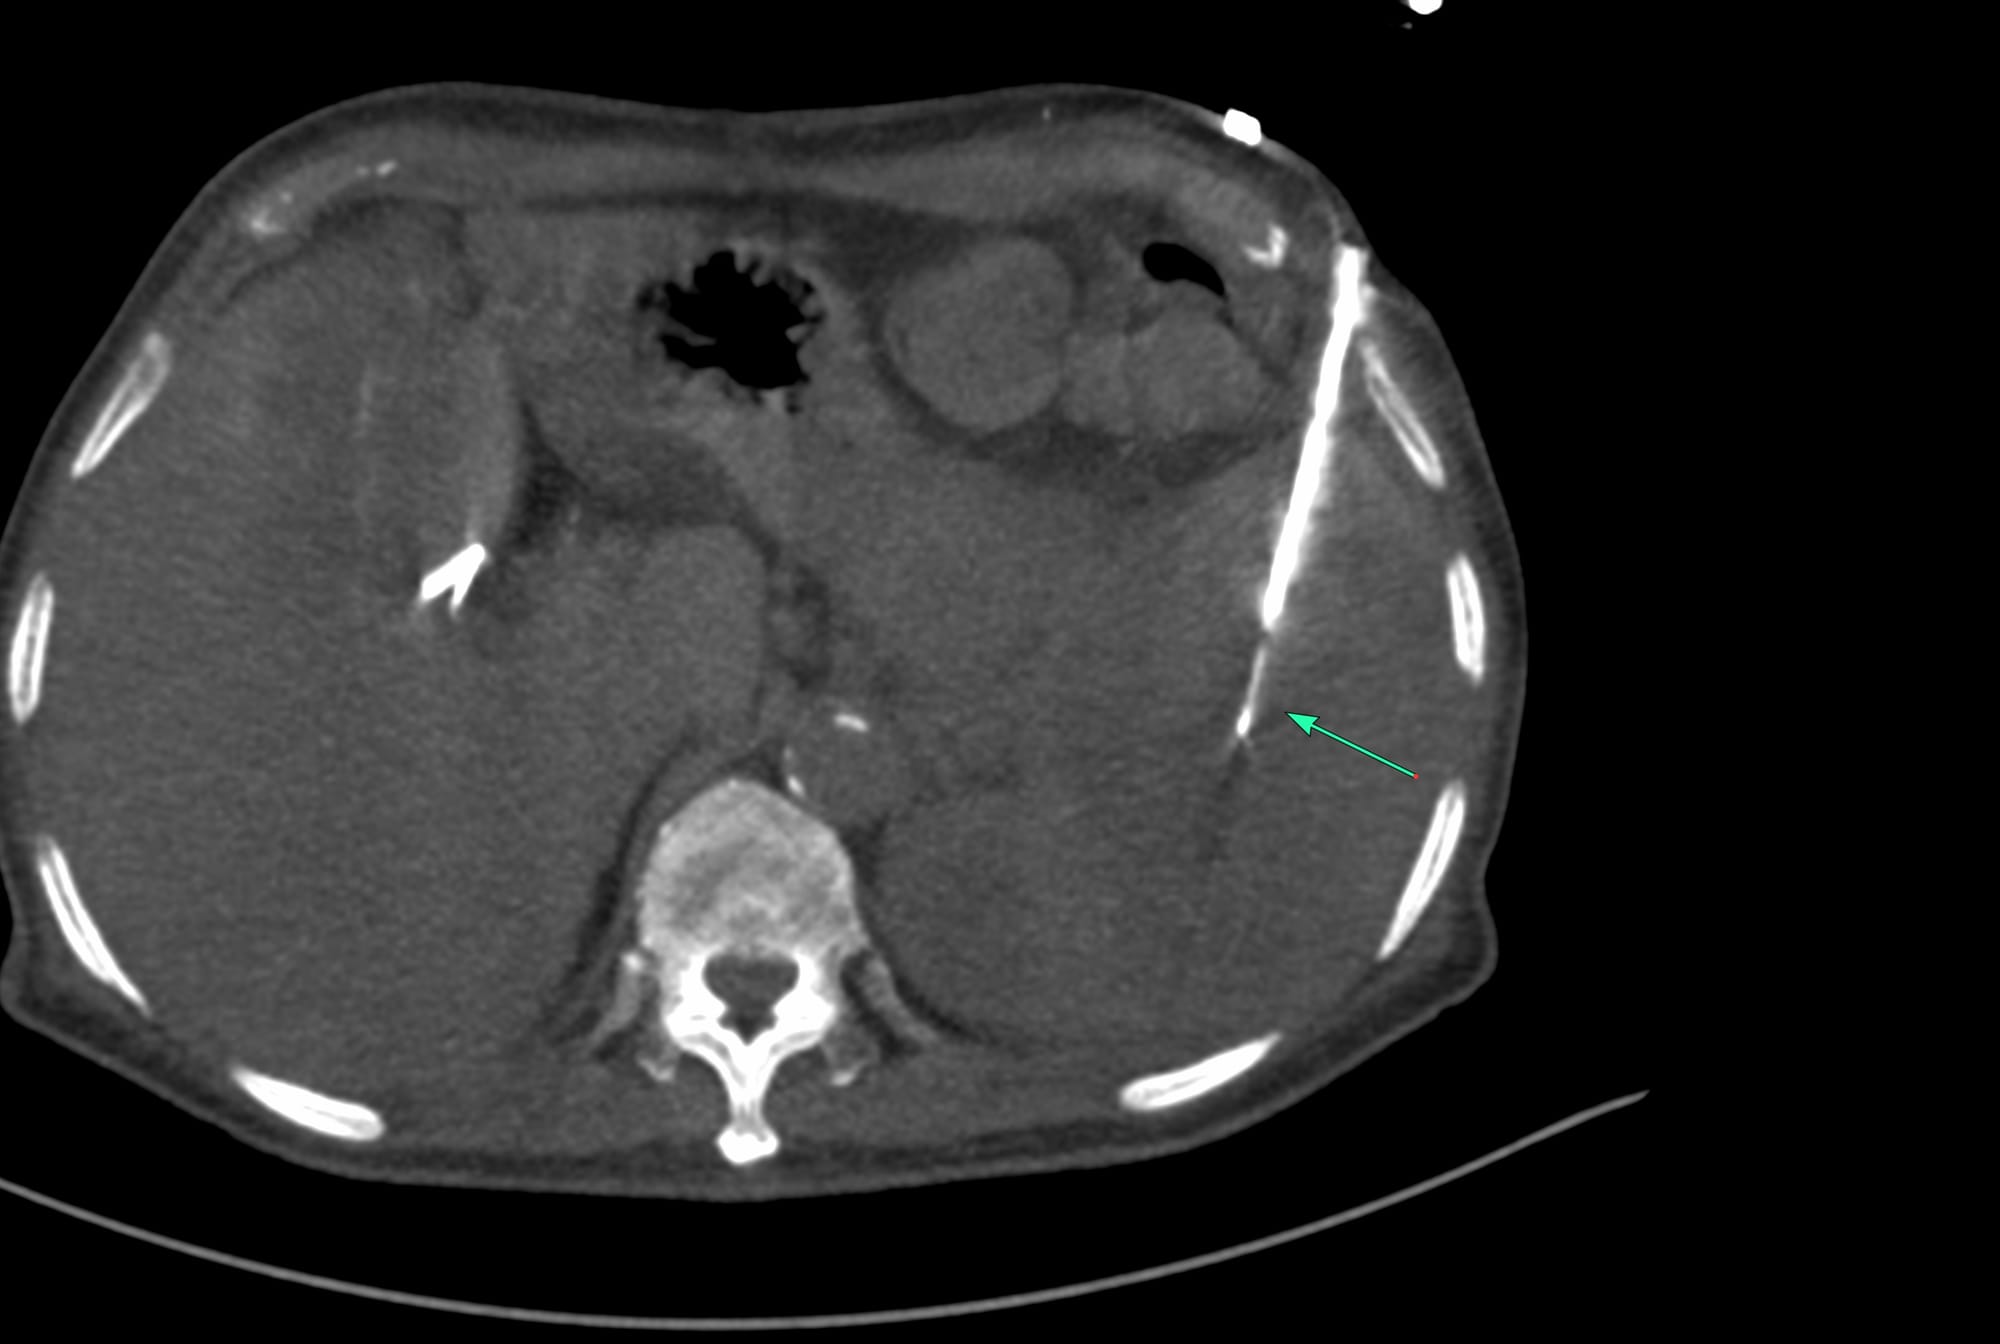

Case 171 - Splenic Mass Biopsy

Case 115: Splenic Lesion Biopsy